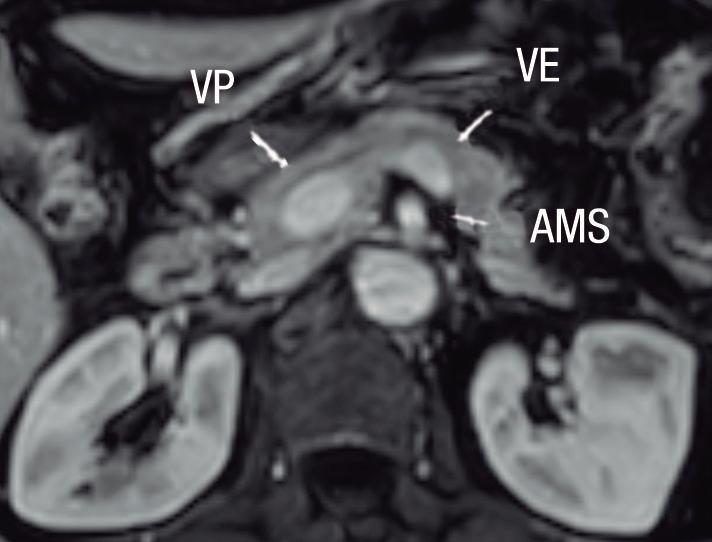

Páncreas Circumportal

El páncreas engloba a la vena mesentérica superior o vena porta, en lugar de rodear al duodeno como sucede en el páncreas anular (Figura 14). Tiene una prevalencia de hasta 2,5% según algunas series, por ende, no es tan infrecuente encontrarlo en estudios por imágenes. Se

A) Resonancia magnética, secuencia T1 sin contraste, plano axial. Tejido pancreático con típica señal hiperintensa en secuencia de ponderación tisular T1 (cabezas de flecha), rodeando a la vena porta (VP). B) Resonancia magnética, secuencia T1 con contraste, fase portal, plano axial. VP: vena porta, VE: vena esplénica, AMS: arteria mesentérica superior.